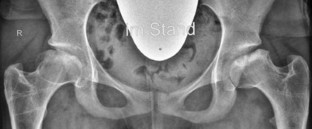

Abb. 1